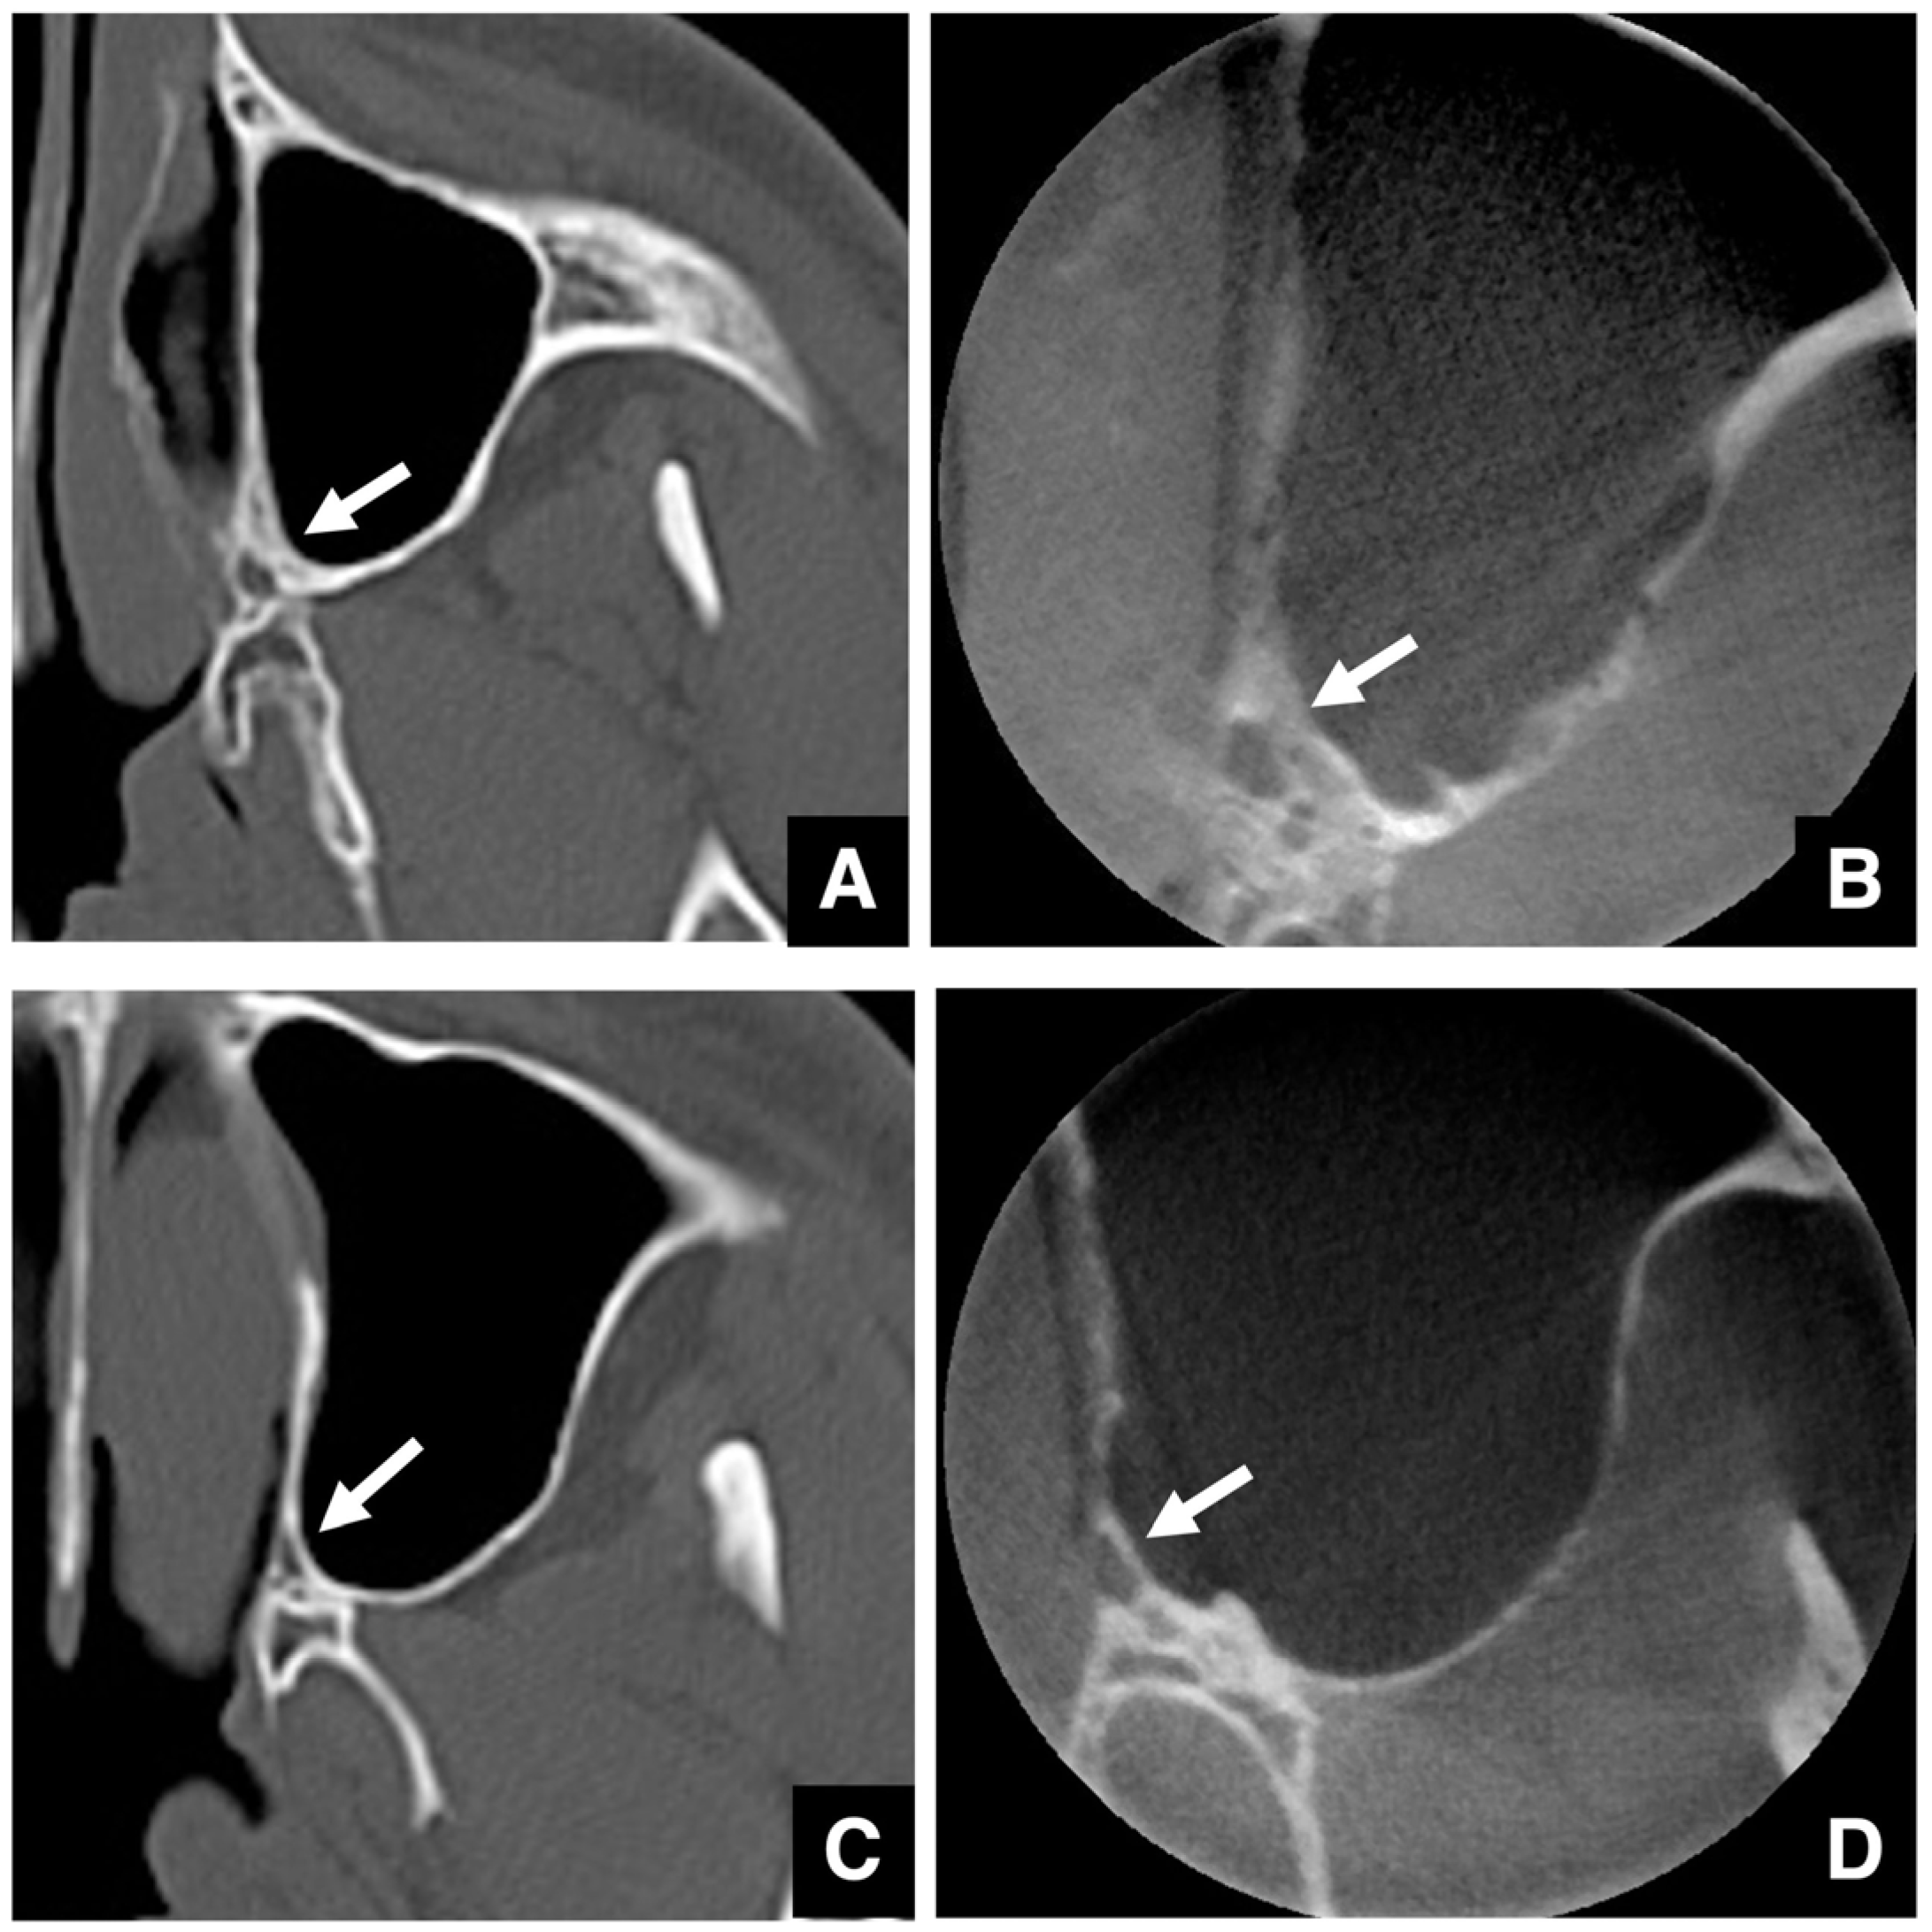

2.6. Imaging Evaluation of the TMJ in Jaw Deformities

- Ünsal, G.; Orhan, K.; Tamimi, D. Imaging of the Temporomandibular Joint Interventions. Neuroimaging Clin. N. Am. 2025, 35, 539–552. [Google Scholar] [CrossRef]

- Riechmann, M.; Schmidt, C.; Ahlers, M.O.; Feurer, I.; Kleinheinz, J.; Kolk, A.; Pautke, C.; Schön, A.; Teschke, M.; Toferer, A.; et al. Controversial Aspects of Diagnostics and Therapy of Idiopathic Condylar Resorption: An Analysis of Evidence- and Consensus-Based Recommendations Based on an Interdisciplinary Guideline Project. J. Clin. Med. 2023, 12, 4946. [Google Scholar] [CrossRef]